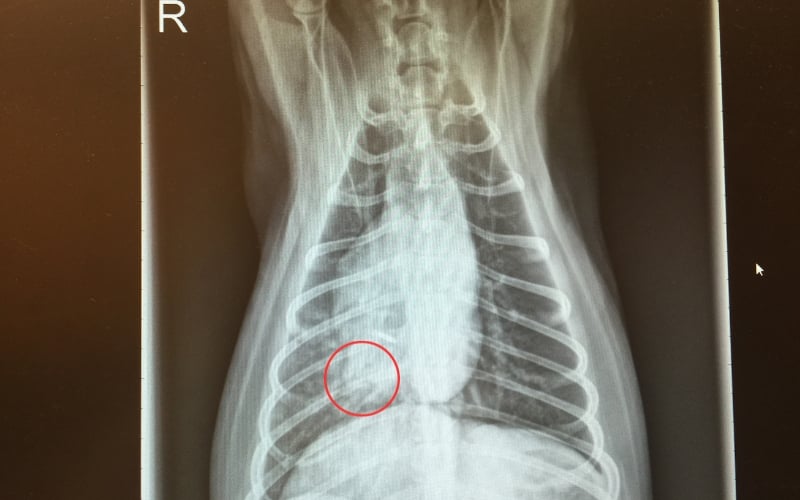

Chest X-Rays

X-rays are very helpful to see changes in the airways consistent with aspiration pneumonia. In some pets, it can take up to 24 hours after an animal aspirates for pneumonia to be seen on X-rays. Once it is seen, X-rays can be used to monitor treatment progress and healing.

The red circle above outlines the alveolar lung pattern in the right middle lung lobe. The right middle lung lobe is a common lobe where aspiration pneumonia occurs. An alveolar pattern indicates that the alveolar air sacs of the lung are completely clogged with debris.